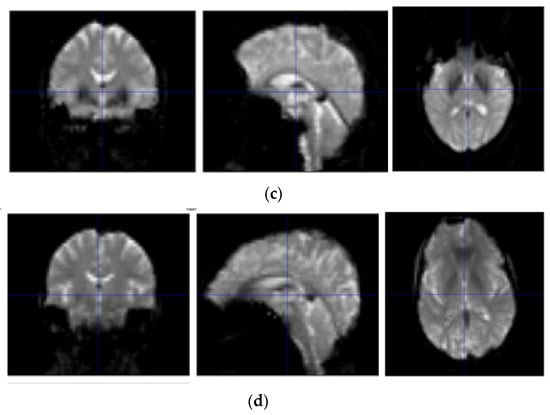

As can be seen from Table 1, with the aggravation of the disease, MMSE scores showed a downward trend, while CDR showed an upward trend. A statistical analysis of basic information was obtained by SPSS software [17]. Sample scanners selected from the ADNI are from Philips Medical Systems. The resting state fMRI scan sequence (EPI) has a total of 140 time points with 48 layers, a magnetic field intensity of 3.0 tesla, a flip angle of 80.0, a TE of 30.0 ms, a TR of 3000.0 ms, a 64 × 65 matrix, and 6720.0 images with a thickness of 3.31 mm. The resting-state fMRI image display of NC, AD, sMCI, and pMCI subjects is shown in Figure 1.

Figure 1.

Resting-state fMRI image display of NC, AD, sMCI, and pMCI subjects. (a) Resting-state fMRI image display of a NC subject; (b) resting-state fMRI image display of an AD subject; (c) resting-state fMRI image display of a sMCI subject; and (d) resting-state fMRI image display of a pMCI subject.